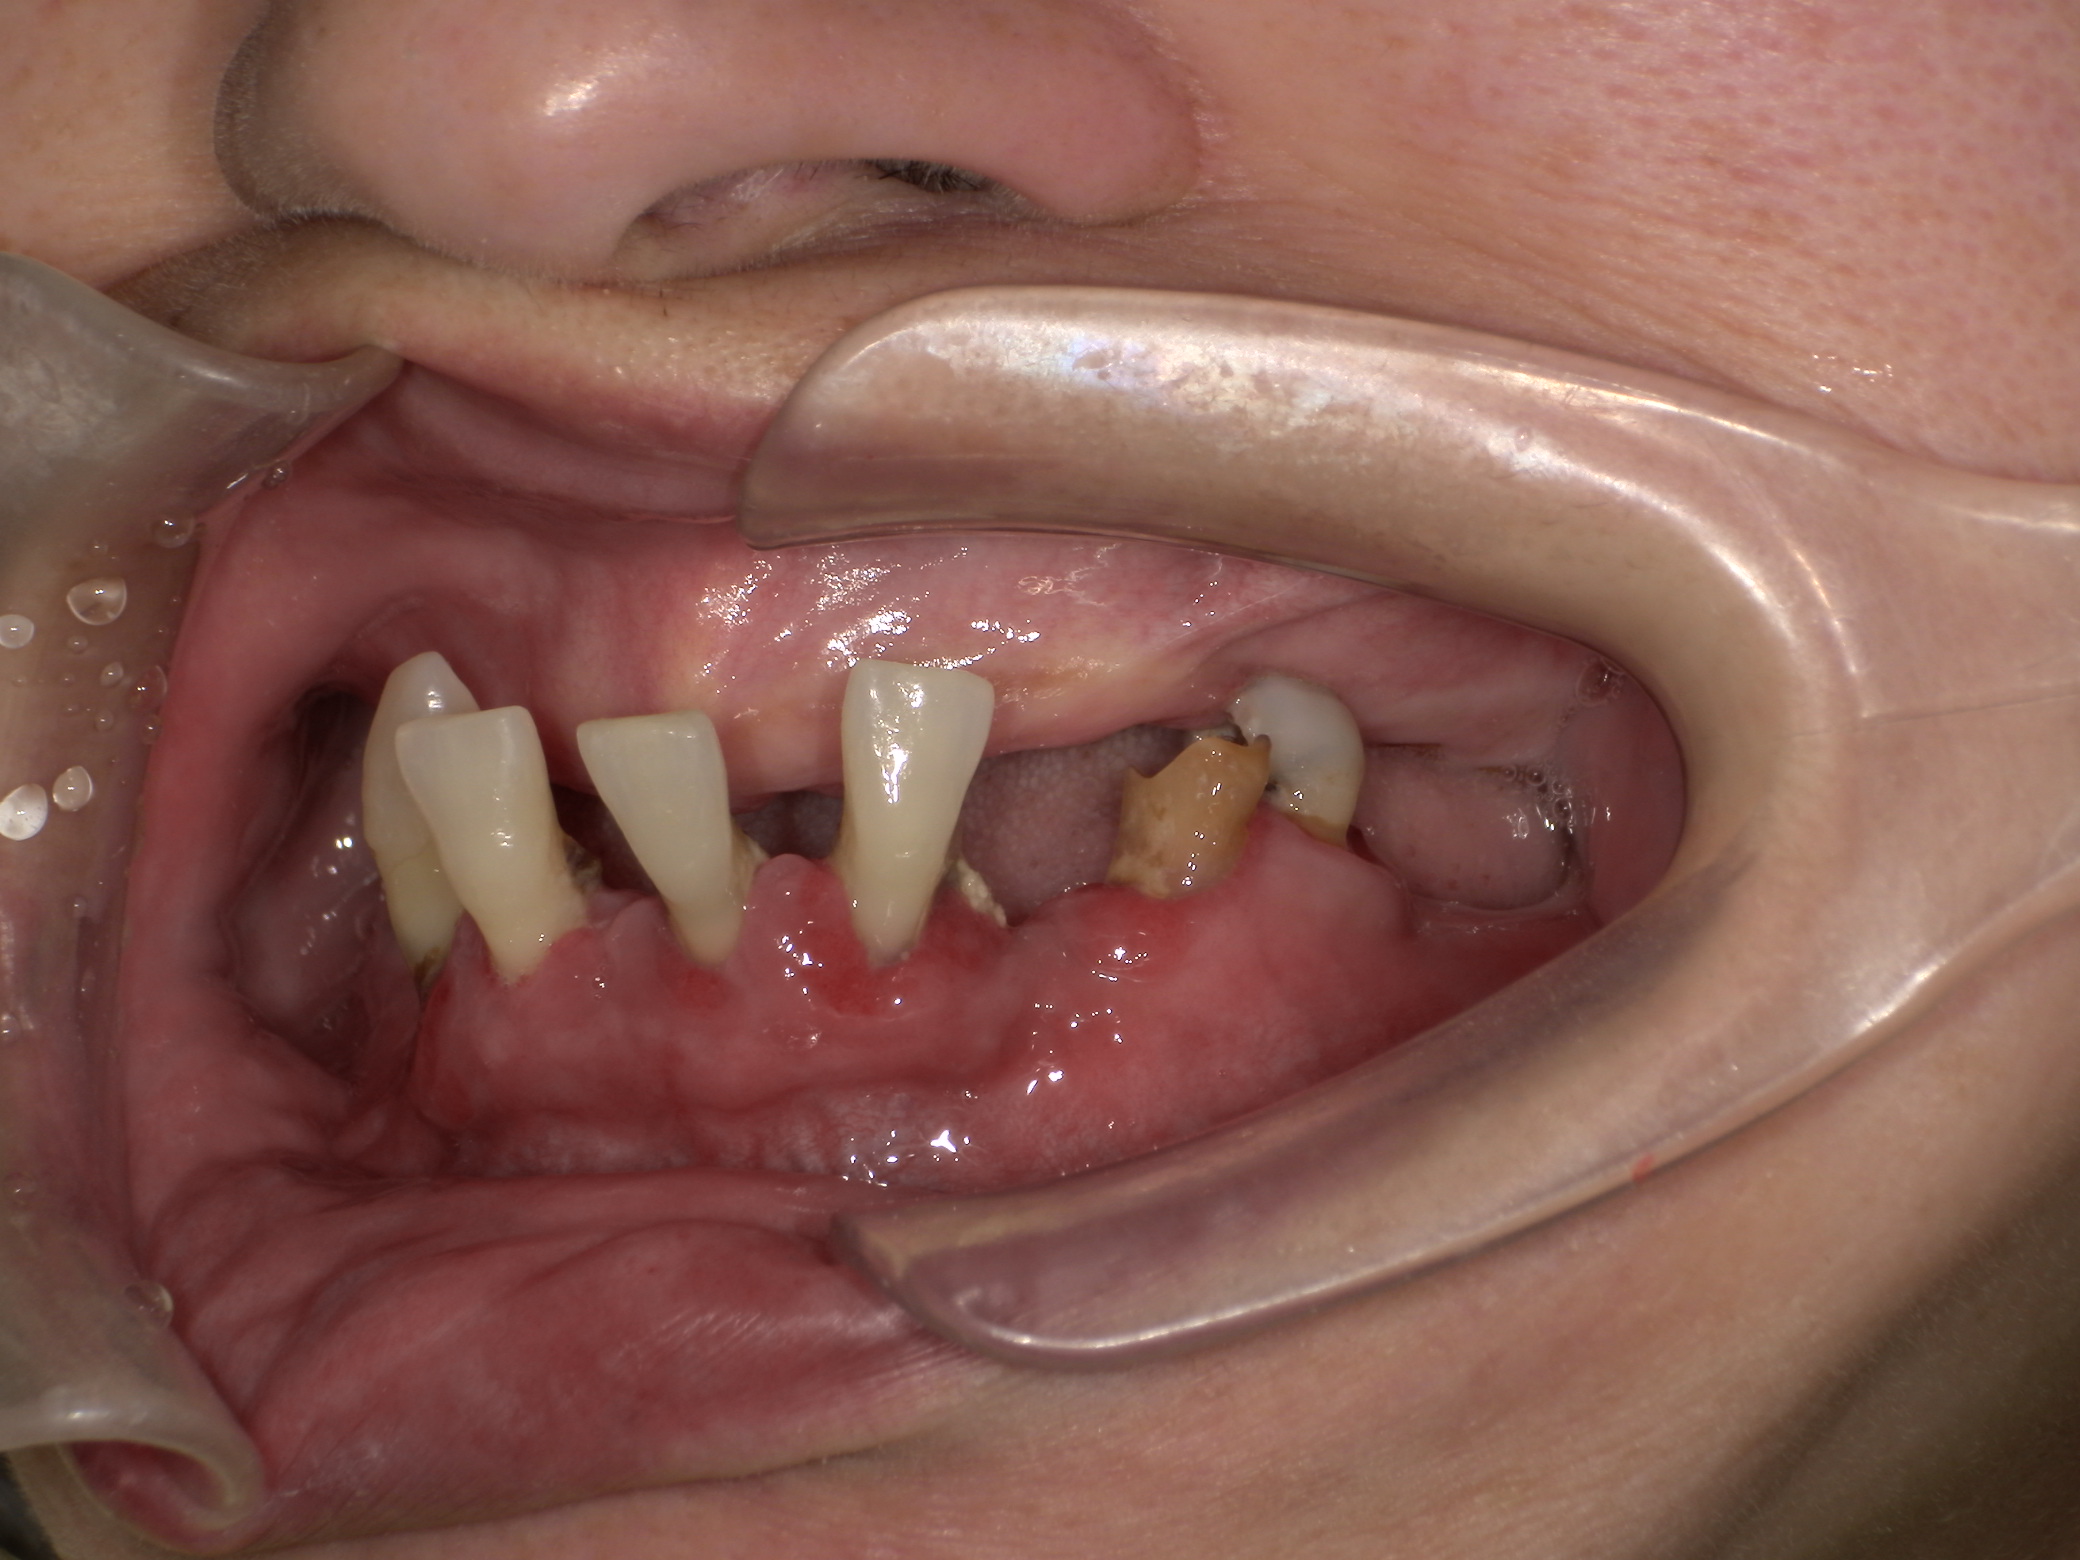

ノンクラスプ義歯症例|噛めなくて困っている。入れ歯使っていない。

2025/12/28 入れ歯